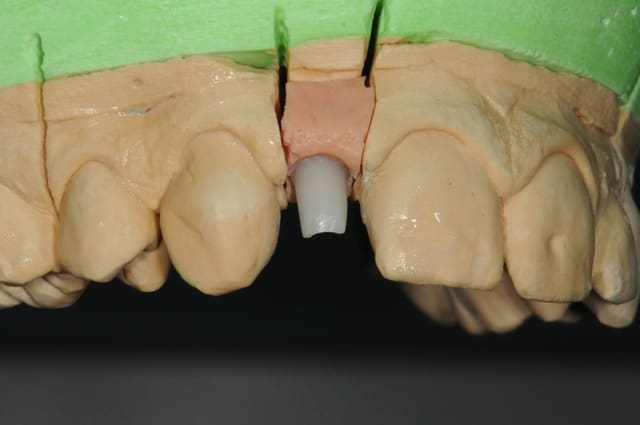

01/09/2010 à 16h54

-1 ou 2 mois plus tard ( je sais plus)

- empreinte avec transfert pop in

- pilier zircone esthétique Axiom

- prothèse et pilier

- pilier zircone en place

- couronne en place (petite compression gingivale)

fin du traitement